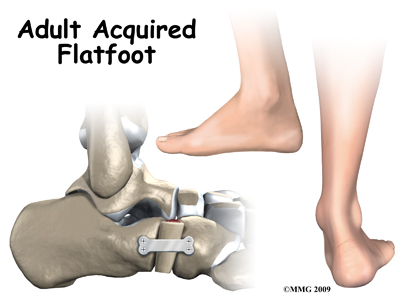

Adult Acquired Flatfoot Deformity

Adult acquired flatfoot deformity (AAFD) is a painful condition resulting from the collapse of the longitudinal (lengthwise) arch of the foot. As the name suggests, this condition is not present at birth or during childhood. It occurs after the skeleton is fully matured.In the past this condition was referred to as posterior tibial tendon dysfunction (or insufficiency) but the name was changed because the condition really describes a wide range of flatfoot deformities, not just those caused by p...